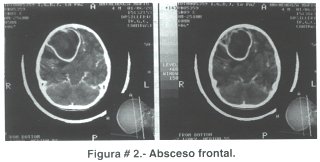

La diseminación directa sucede en 20 a 60% de casos y usualmente da lugar a un absceso simple; cuando el origen es otomastoideo el asiento de la infección generalmente es el lóbulo temporal y el cerebelo (figuras # 1 A y B), en tanto que los frontales y parietales (figura # 2) son afectados cuando la infección parte de los senos paranasales (maxilares, etmoidales, frontales) o abscesos dentarios(5).

Tanto la resonancia magnética como la tomografía computarizada son pruebas que definen el diagnóstico de absceso cerebral; con ambas se puede establecer claramente el área de cerebritis, la cápsula y el edema perilesional (figura # 2), sin embargo a IRM se le otorga mayor utilidad al momento de precisar el diagnóstico frente a masas tumorales o abscesos con tendencia a romperse en el sistema ventricular(10,13), asimismo cabe destacar que es un método más sensible en la detección de cerebritis temprana, para observar lesiones satélite, visualizar mejor el tallo cerebral y es más segura para estimar la extensión de la necrosis central. La resolución de la TAC es suficiente para definir el diagnóstico de AC; en etapas tempranas el parénquima cerebral comprometido se caracteriza por cambios de baja densidad mal definidos, para posteriormente, al momento de administrar medio de contraste, observar el clásico anillo bien definido de la cápsula rodeada de edema. En la mayoría de casos el absceso es único, sobre todo cuando el origen es una infección de senos paranasales y otomastoides, en cambio cuando la siembra es hematógena existe mayor tendencia a la formación de abscesos múltiples e incluso multilobulados(14) (figura # 4 A y B).